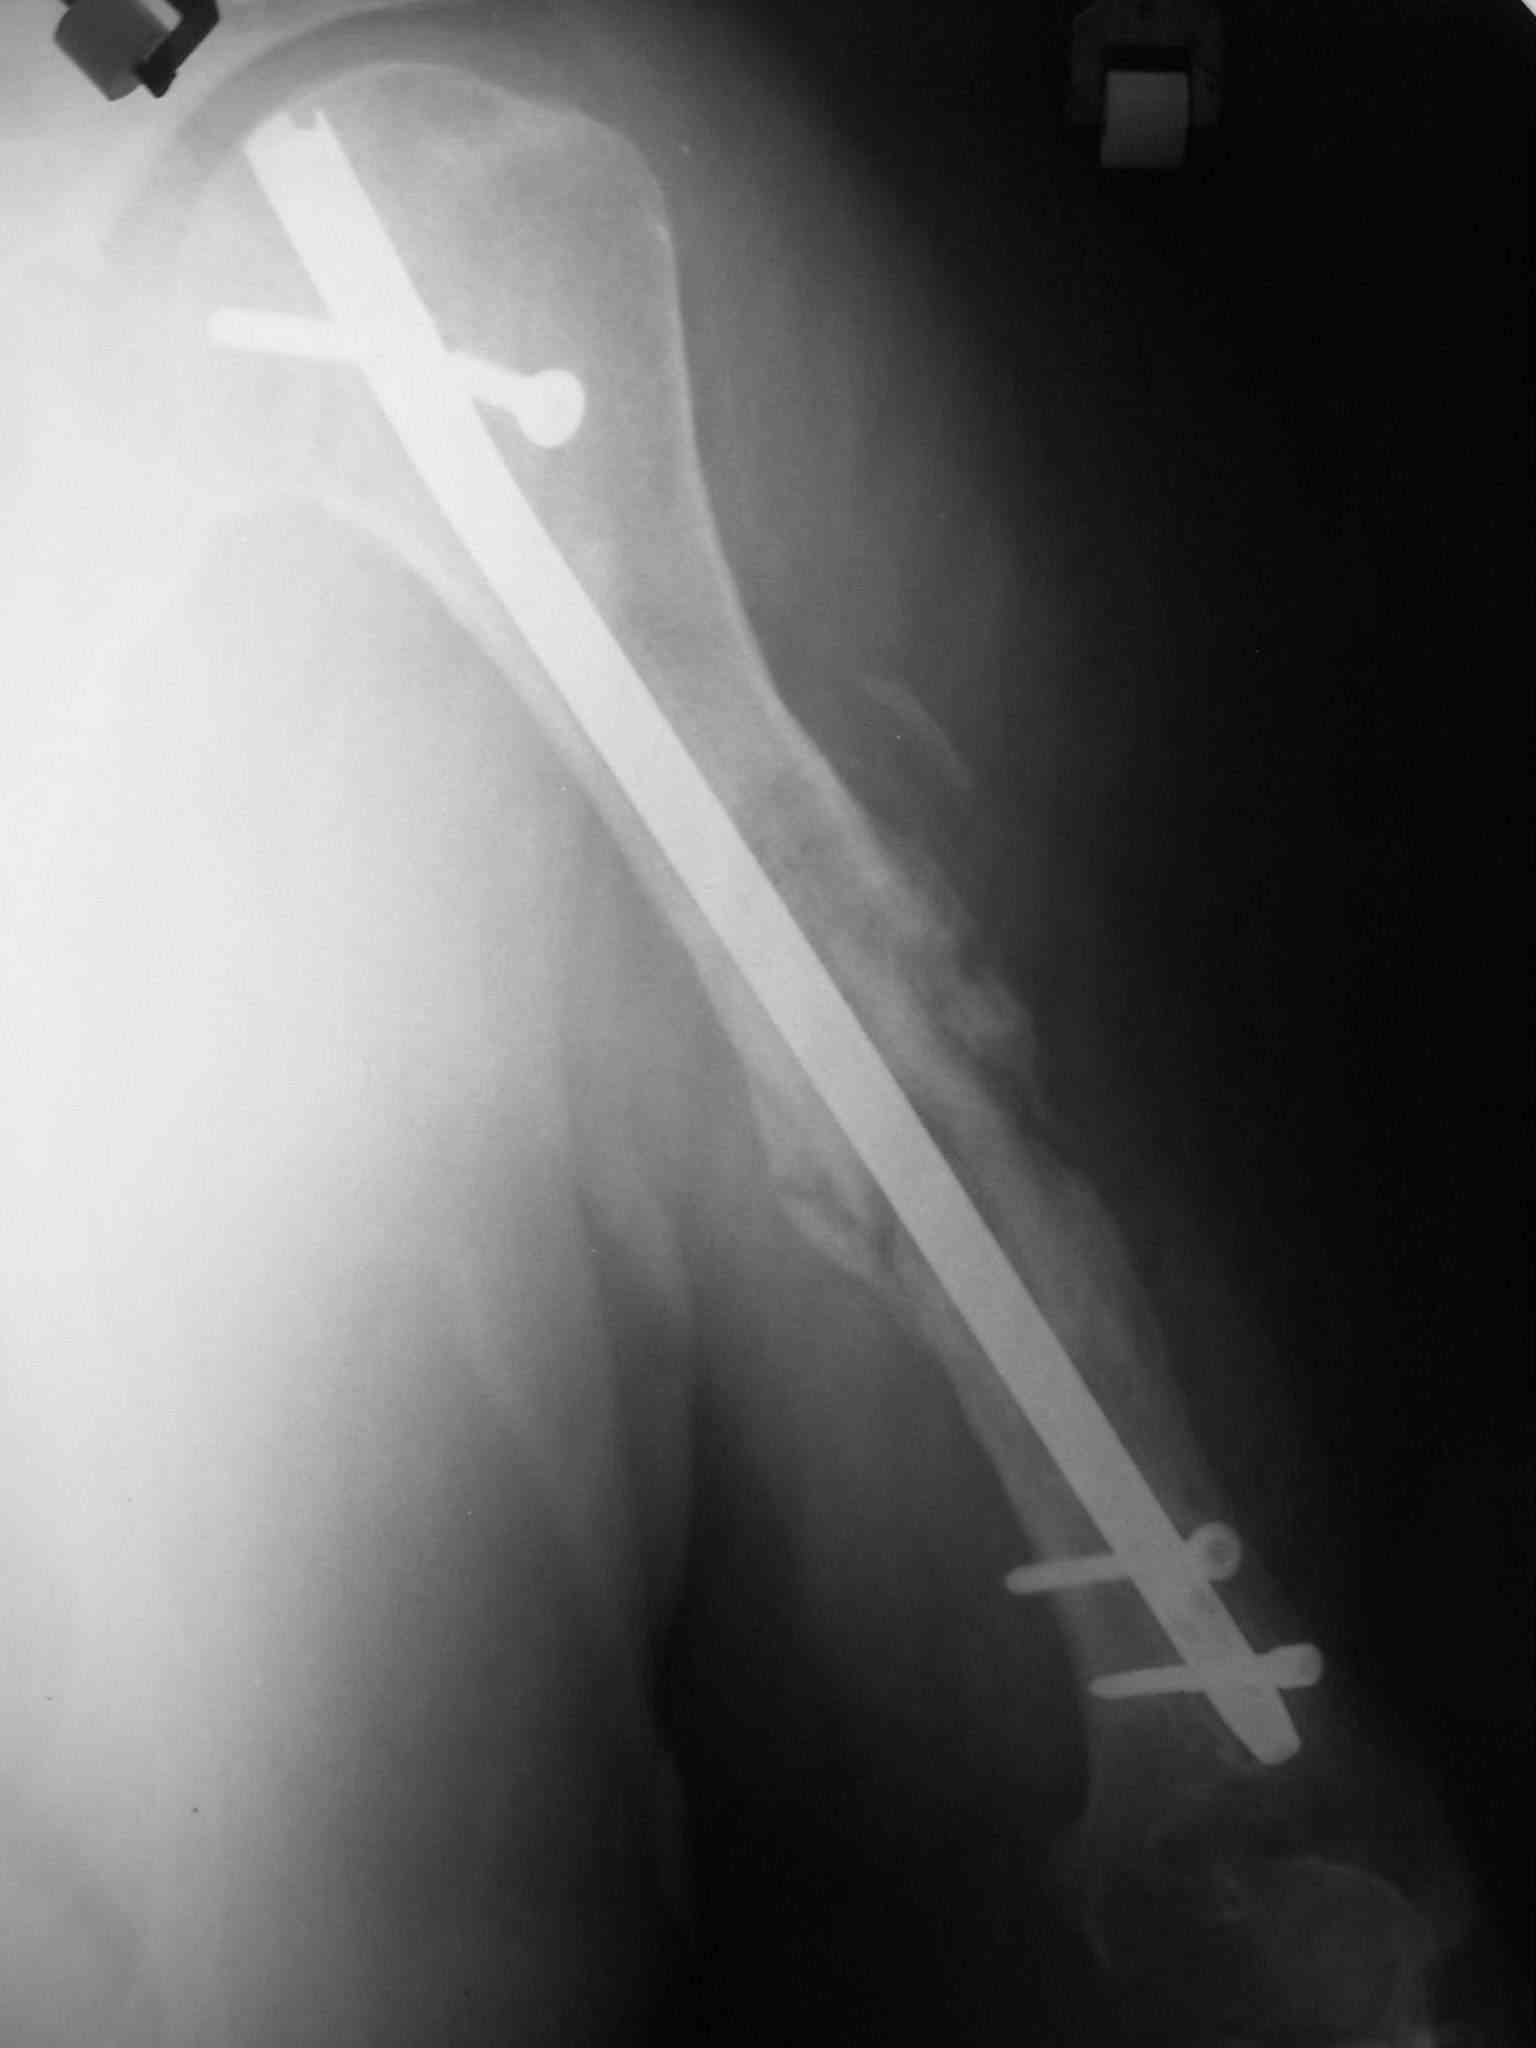

Объективно очевиден лишь тот факт, что не смотря на варианты фиксации перелом несрося за 1.5 года, и по снимку речь вряд ли идет о рефрактуре. Отрицать предположение А.Н.Челнокова о дремлющей инфекции при отсутсвии объективных методов исследования более чем не обосновано. Риск септического воспаления выше чем при первичном остеосинтезе, поэтому выбран более надежный препарат профилактики.

Ну это уже хоть что-то. Вполне может, по этим снимкам показалось, что там периостальные наоения какие-то... остеомиелитно-подозрительные.

На Вашу ситуационную задачу: у нас был аналогичный случай (у пациента Д. за три года было девять ранее перенесенных операци: штифт Богданова с гипсом-пластина-нагноение- аппараты-лечение гнойных ран и остеомиелита - опять dcp пластина-разрушение и миграция пластины....) -

БИОС делали открыто, с декортикацией, частичным торцеванием и костной аутопластикой. Вариант БИОС - компрессирующий). Насчет компрессирующего варианта БИОС потом пожалели - проксимальный блокируемый винт сломался через год, надо было делать стабильный вариант.